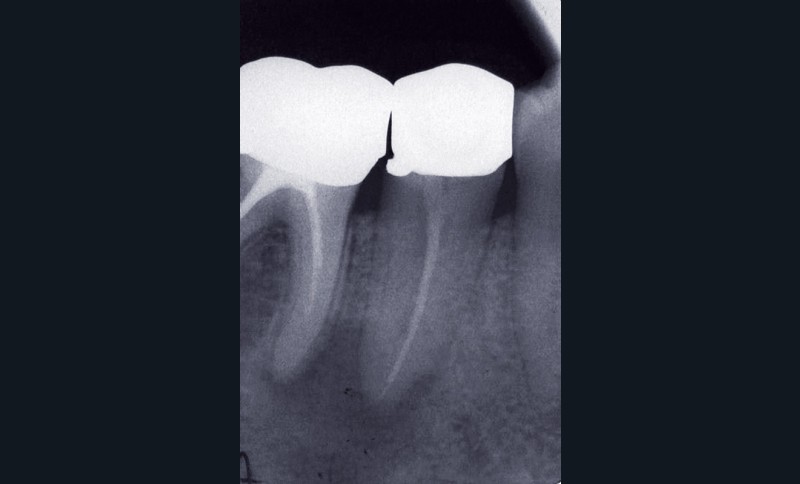

Traitement en une ou plusieurs séances ?

S’il est admis aujourd’hui qu’il est préférable de traiter endodontiquement les dents exemptes de lésions apicales en une seule séance [8], la question reste posée pour les dents affectées d’une LIPOE. Faut-il procéder de façon systématique à une phase de médication temporaire au cours du traitement endodontique des dents porteuses d’une lésion péri-apicale ? Certains auteurs [1, 35, 39] préconisent la mise en place d’une phase d’hydroxyde de calcium (CaOH2) afin d’obtenir un canal exempt de bactéries. À l’inverse, d’autres études [7, 24, 25, 40, 46] s’accordent sur le fait qu’il n’y a pas de différence significative entre le traitement en une ou plusieurs séances des dents porteuses d’une PAC, en termes tant de taux de guérison que de complications postopératoires (fig. 6).